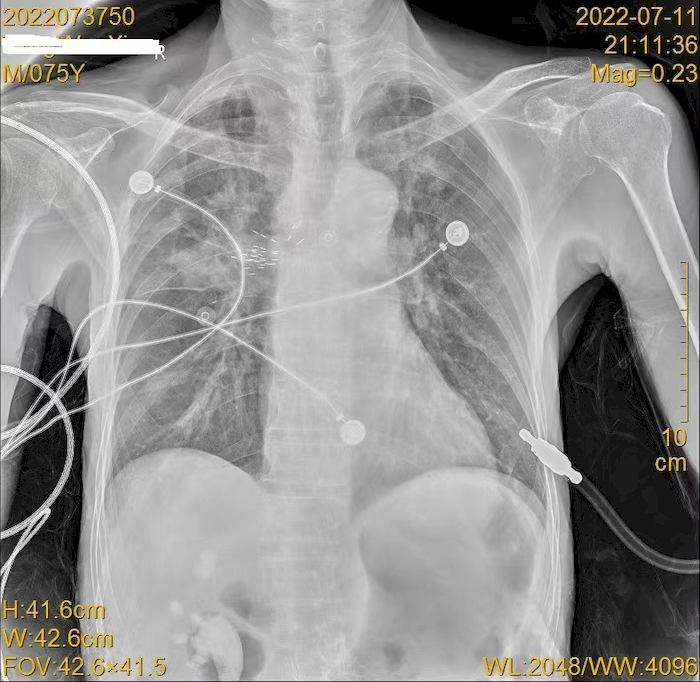

放射性粒子植入术后复查胸片查看粒子位置。于涛供图